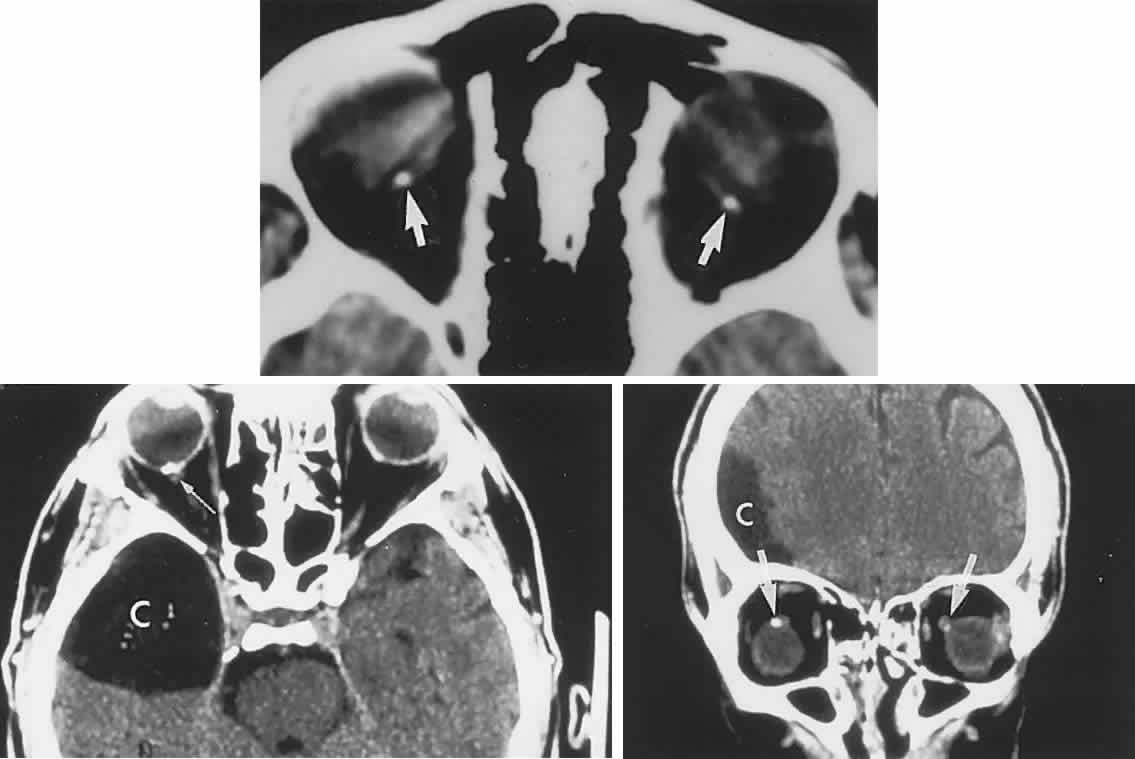

Microangiopathy of the brain, retina, and inner ear (Susac's syndrome) is a rare disorder predominantly affecting women of child-bearing age, but without a specific origin or systemic manifestations. An immune or coagulopathic background is unproved. Patients present with the following: vision loss due to branch retinal arteriolar occlusions with vessel hyperfluorescence on fluorescein angiography, and delayed leakage; hearing loss; multiple CNS infarctions.113 Efficacy of treatment with corticosteroids and immunosuppressive agents is uncertain, but hyperbaric oxygenation has been beneficial in a single case, with rapid visual improvement.114